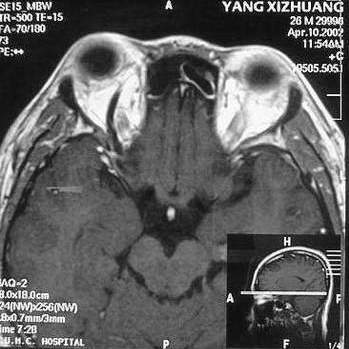

MRI及增强结果如下:

患者压颈及其它Valsava试验结果阴性。从MRI分析,在T1、T2、T+C检查该支血管均为明显流空现象,说明该血管血流速度很快,而从走行和分布看,眼上静脉可能性很大。也许也不能除外异常的眼动脉或异常血管。眶内主要可能的血管病变包括颈内动脉海绵窦瘘(高流窦)、AVM、眼眶静脉曲张、海绵状血管瘤、静脉性血管瘤、毛细血管瘤和眶内动脉瘤。。

1、颈内动脉海绵窦瘘:该患者临床有一部分支持该诊断。但从影像分析,海绵窦未见明显扩张;眼外肌未见明显充血扩张的长T1、长T2信号;颈内动脉海绵窦瘘常可见继发到血栓,可见到短T1、长T2的血栓信号。

2、眼眶静脉曲张:该疾患一般常见于小儿。该患大多数会出现Valsava试验阳性,间歇性突眼。不符合该患。影像学检查,于曲张静脉内常可见血栓和静脉石。所以不符合该患。

3、AVM:患者目前的影像学资料尚不全面,但可符合该诊断。临床上改病常见于30岁左右年轻人,单侧发病,于本患较符合。问题在于临床没有明确的血管杂音,似乎难以解释。

纵上所述:本人觉得,患者AVM可能性较大,同时不能除外眶内动脉瘤。